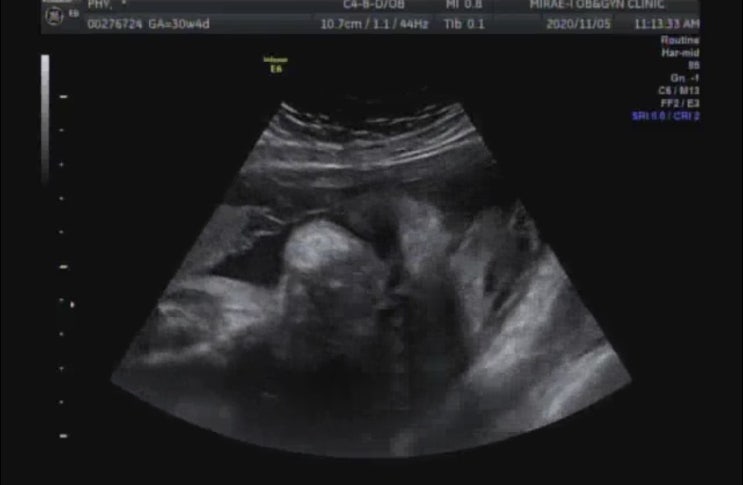

임신 29주, 자가격리 2주 - 임신 32주 배통증, 분비물증가, 태동통증, 백일해주사

#임신32주 #백일해주사 #임신9개월 #태동통증 #임산부자가격리 #자가격리2주 22일 아침. 출근하려는 남편을...